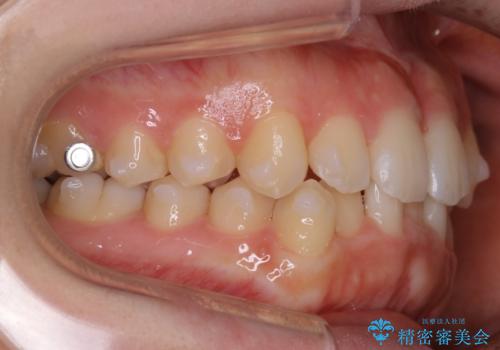

【非抜歯】すきっ歯と噛み合わせの治療

- 上の前歯のすきっ歯と下の前歯のガタつきを主訴にご来院されました。

噛み合わせの改善も同時に進めつつ、主訴の部分も効率的に治していくためマウスピース装置でゴムかけを行いながら治療を進めていきました。

正中離開(すきっ歯)

真ん中の歯が左右に開いてしまい隙間ができてしまう状態を「正中離開」といい、俗にすきっ歯と呼ばれています。

隙間を埋めていく方向に歯を移動させることで改善していくケースが多く、比較的治りやすい不正咬合のひとつとされています。

しかしながら、歯が捻じれていたり、噛み合う歯との位置関係によっては治療が難しくなる場合があります。